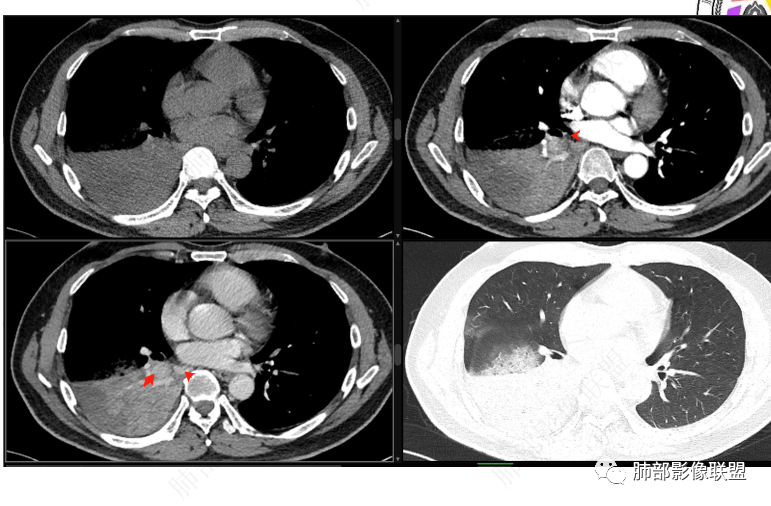

首先血管未见明显侵犯、移位,提示病灶:炎性;肿瘤:外朝内——含粘液类腺癌(肺门淋巴结转移),腔内肿瘤(鳞癌、腺癌、类癌、小细胞、粘液表皮等)

从强化看:外周密度低,强化弱

就不太符合腔内肿瘤远端不张的表现,因为外围不张——强化明显

这一例反了

按这个特点周围要考虑肿瘤组织

腔内肿瘤,远端堵塞

这个外面明显也是肿瘤部分

可能含有粘液所以这么低

我觉得粘液表皮可能要放前面

腔内

按理类癌远端密度不会这么低

而且我认为近端实变区强化与附近高密度影是否与感染有关